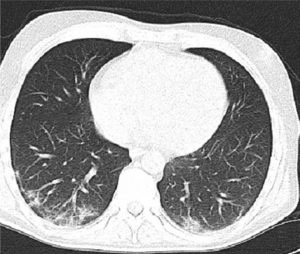

وأوضح مدير المشفى والمشرف على الحالة الدكتور أحمد عباس أن الشاب راجع شعبة الأمراض الهضمية بحالة هجمة التهاب قولون قرحي حاد مختلطة بالتهاب رئوي كوفيد 19 وسارس كوف 2 إضافة إلى أنه يعاني من الإسهال الدموي من 6 إلى 8 مرات في اليوم وارتفاع في الحرارة 38.9 درجة مئوية وآلام مغص حادة في البطن مع تشخيص قولون في الجانب الأيسر قبل ستة أشهر من مراجعته المشفى.

وأشار الدكتور عباس إلى أنه تم إجراء الفحوص والاستقصاءات الطبية ودراسة متكاملة لحالة المريض بالتعاون والتنسيق مع الكوادر الطبية الأخرى مبيناً أن التوصيات الطبية تتضارب حول مشاركة العلاج البيولوجي مع علاج كوفيد 19 عند الهجمة الحادة للمرض إلا أن المريض لم يستجب على جرعة عالية من الستيرويدات.

ولفت الدكتور عباس إلى أنه تم اتخاذ القرار بعلاج الحالة بالأدوية البيولوجية بإشراف ومتابعة لحظية من قبل الاختصاصيين وتقديم كل ما يلزم حتى تماثل للشفاء وتم تخريجه من المستشفى بحالة جيدة ومستقرة.